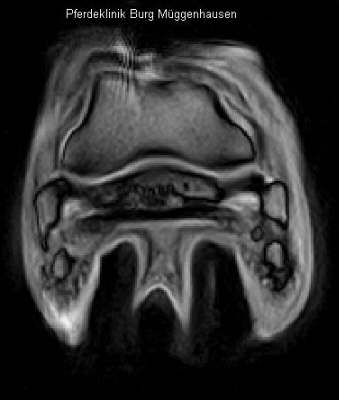

Deutliche Strahlbeinveränderungen und ebenfalls Nachweis des Gleitflächeneinbruchs in das Strahlbein.